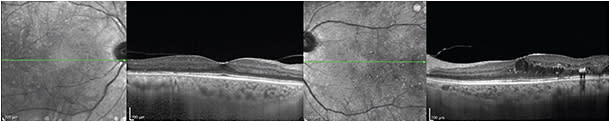

The choroid is thicker in CSR (Figure 1) than in normal eyes (414-478 µm vs 248 µm, respectively), and the choroidal vascular lumens appear enlarged.11 In chronic CSR, a “double layer sign” may appear, with an undulating RPE layer, hyporeflective middle layer, and intact Bruch’s membrane.11

Figure 1. Central serous retinopathy. A healthy 28-year-old man complained of metamorphopsia for five days after undergoing a tooth extraction. On examination, he had BCVA of 20/20 OD and 20/40 OS and an elevated macula on dilated fundus examination. EDI-OCT exhibited prominent subretinal fluid and thickened choroids in both the affected and unaffected eyes.

CREDIT: ALL IMAGES, PATRICIA GARCIA, MD

The unaffected fellow eye may also be thickened. With indocyanine green angiography, up to 65% of patients demonstrate hyperpermeability in the contralateral eye, which may account for the 20-30% incidence of bilateral disease in longitudinal observational studies.11,12

After spontaneous resolution of CSR, the choroidal thickness decreases but does not return to normal. Photodynamic therapy causes a greater change than spontaneous resolution; studies have shown initial swelling of approximately 58 µm, followed by a reduction to normal thickness. Laser photocoagulation did not significantly affect choroidal thickness.12,13